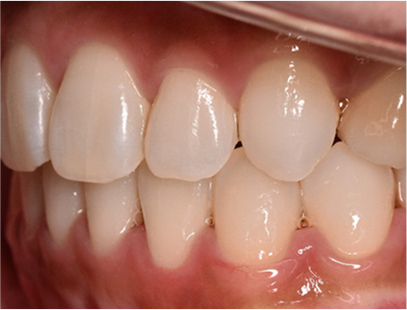

• 左側

• 右側